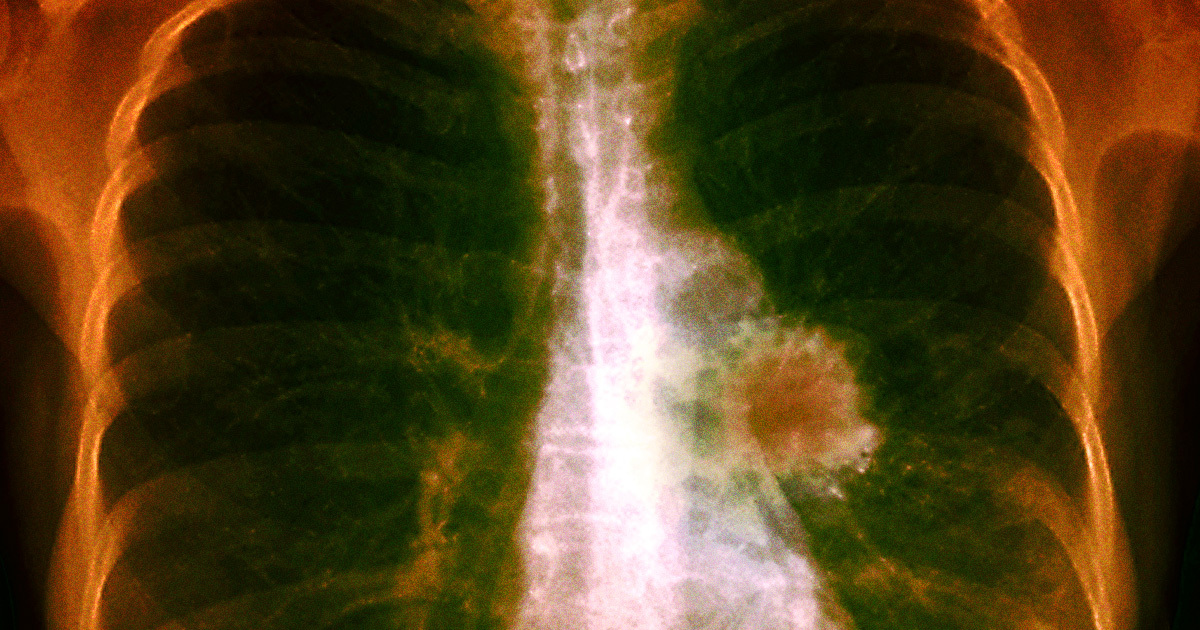

A five-year study published in The New England Journal of Medicine has shown that the lung cancer pill, Osimertinib (Tagrisso), can reduce the risk of recurrent cancer by up to 73% and the risk of death by up to 51% in patients with Stage 1B-3A lung cancer who have a certain genetic mutation and have had surgery to remove cancerous tumors. The results have been described as "earth-shattering" by experts in the field, as the improvement in survival rates far exceeds previous expectations. The pill is part of the growing field of personalized medicine, targeting specific genetic mutations in tumors, and offers hope for lung cancer patients who were previously considered to have a fatal disease.